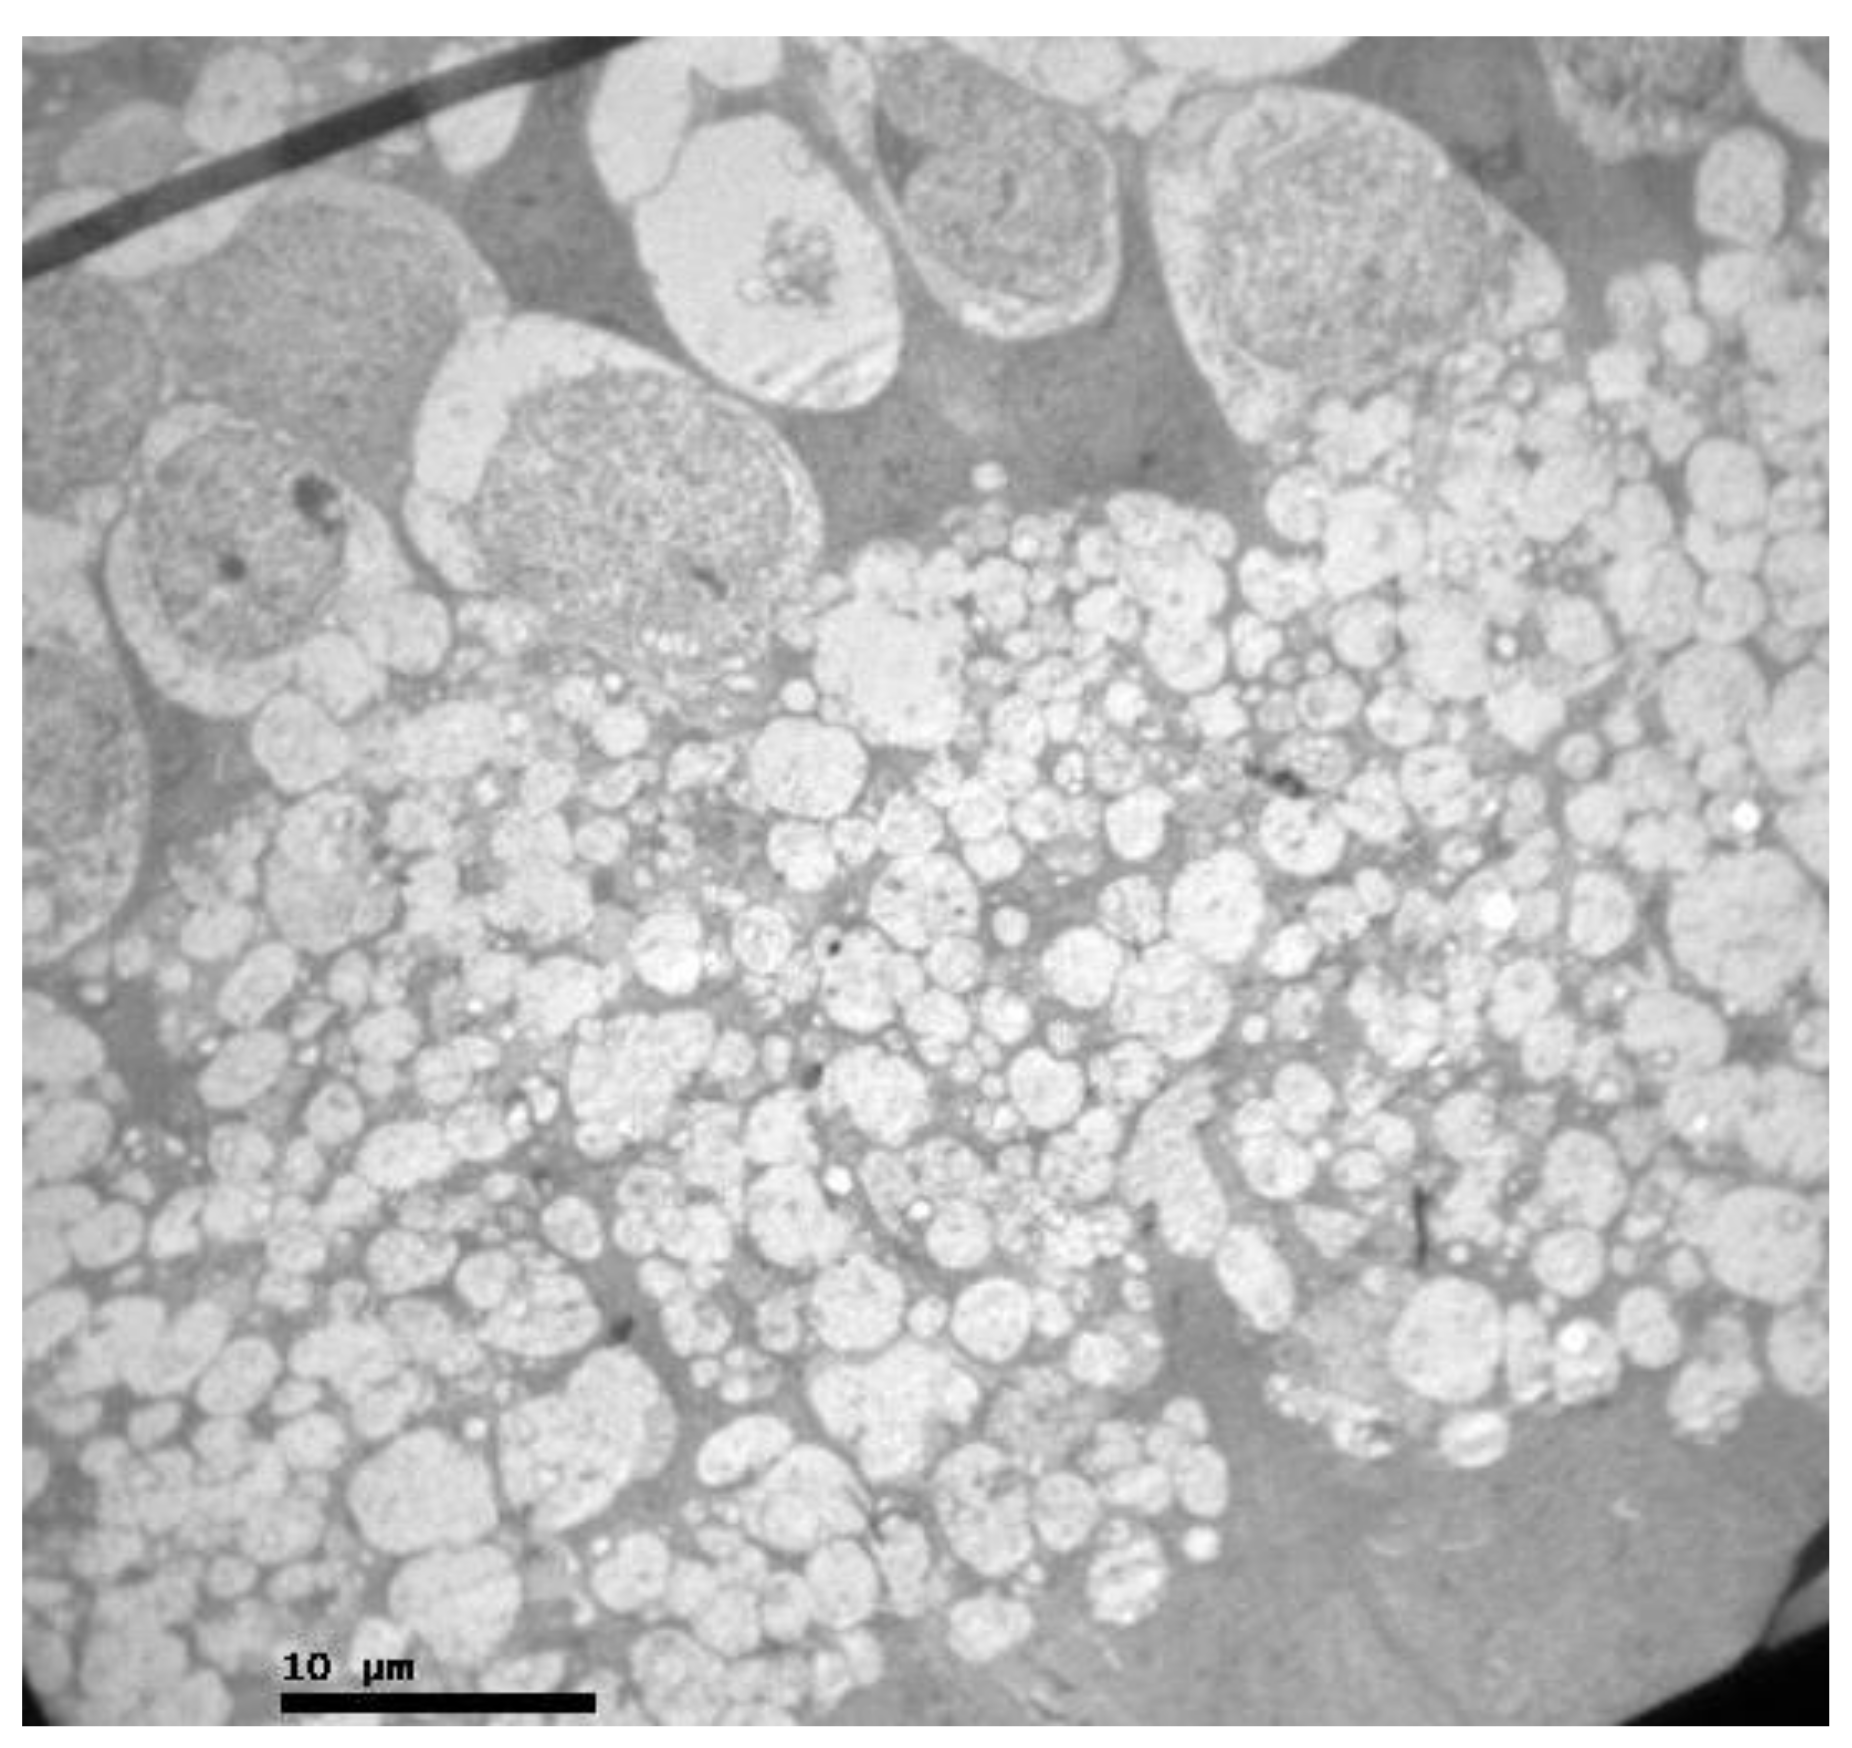

2.2. Group V